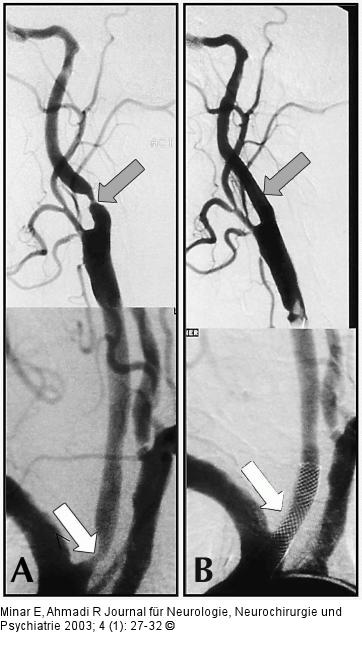

Abbildung 6A-B: Arteria carotis - Stenose - Stent A) Abgangsstenose der A. carotis communis rechts sowie hochgradige Stenose der A. carotis interna rechts; B) angiographisches Ergebnis nach erfolgreicher Stentangioplastie im Bereich der A. carotis communis und der A. carotis interna |